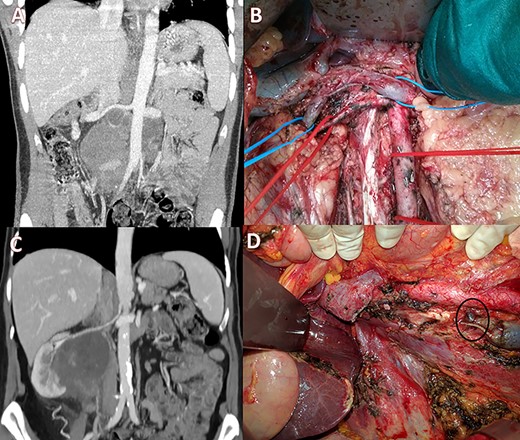

(A) Pre-operative CT scan with a large lesion involving the IVC; (B) intraoperative view showing ligation of the IVC with renal-vein preservation; (C) coronal CT scan with a huge retroperitoneal space-occupying lesion infiltrating the right kidney and occluding the IVC; (D) intraoperative image after right nephrectomy and IVC resection showing a large collateral lumbar trunk (circle).

Case 2 was a 23-year-old male with a testicular germ-cell tumor and evidence of pathologically enlarged abdominal and cervical lymph nodes. After surgical excision of the primary tumor and administration of four cycles of Bleomycin, Etoposide and Platinum (cisplatin) (BEP) + four cycles of paclitaxel, ifosfamide and cis-platinum at another institution, the patient was referred to us. CT scan showed stable disease with a large infrarenal inter-aortocaval mass (13 × 10 cm) obstructing the IVC (Fig. 2A). Extensive abdominal lymphadenectomy and resection of the infrarenal IVC without prosthetic replacement was performed (Fig. 2B). Concurrently, ear−nose and throat surgeons performed modified radical left neck lymphadenectomy. The post-operative course was characterized by transient renal failure and moderate anemia requiring blood transfusions and rehydration therapy. The patient was discharged 13 days later and had normal renal function values and no relevant inferior limb edema. Histology confirmed the diagnosis of lymph node metastases of the germ cell tumor.

Case 3 was a 65-year-old woman with a 9 × 7 cm retroperitoneal mass infiltrating the right kidney and the IVC with radiologic evidence of IVC and right ureteral obstruction (Fig. 2C). Percutaneous biopsy was compatible with angiomyosarcoma. Clinical examination showed no edema of the lower limbs. Neo-adjuvant chemoradiotherapy (doxorubicin + dacarbazine followed by 50 Gy in 25 fractions) was performed. Post-treatment positron emission tomography scan imaging showed stable disease with partial metabolic response. Subsequently, the patient underwent radical resection of the tumor with right nephrectomy and infrarenal IVC resection. No IVC reconstruction was performed and at surgery, venous outflow through a collateral venous lumbar vein was noticed and preserved (Fig. 2D, circle). No major perioperative complications occurred. Post-operative ultrasonography revealed normal lower limb venous pathways and the patient was discharged on post-operative day 11. Histological examination confirmed a leiomyosarcoma grade 2 Fédération Nationale des Centres de Lutte Contre Le Cancer (FNCLCC criteria) with large post-chemotherapy areas of necrosis.